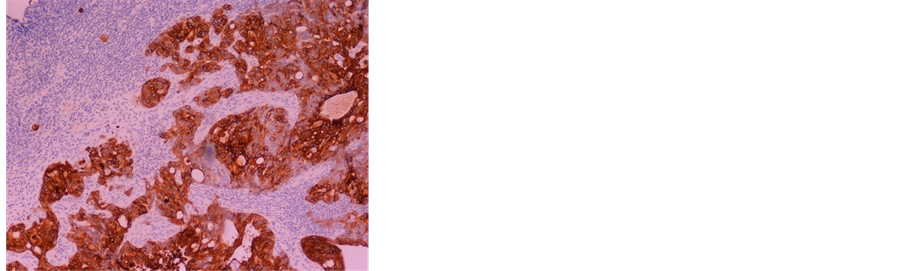

A biopsy of the axillary lymph node was undertaken, and its histologic evaluation showed structures of adenocarcinoma involving lymphoid parenchyma, with expression of the marker CK 20, compatible with a colon cancer metastasis (Figure 3(a) and Figure 3(b)).

Figure 3. (a) Presence of neoplastic structures with glandular and cribiform pattern in the middle of lymphoid parenchyma, with epithelial proliferation and atypia, compatible with metastatic adenocarcinoma; (b) Expression of the immunohistochemical marker CK20 in the tumoral cells, which in the clinical context is compatible with a colorectal cancer.